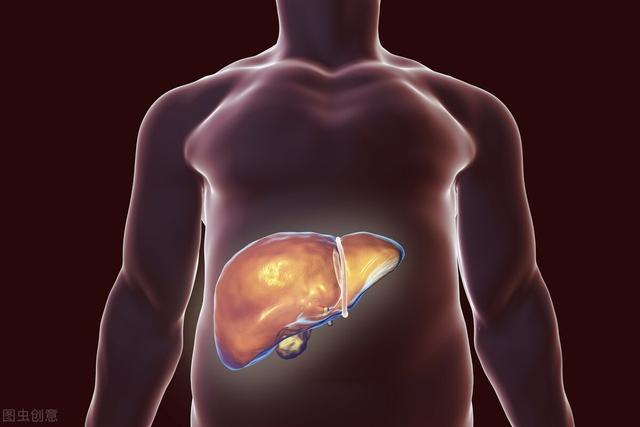

Cirrhose du foie → cancer du foie

Il existe une trilogie d'apparition du cancer du foie en Chine : hépatite → cirrhose → cancer du foie.Les plus courants à l'étranger sontCirrhose due à l'alcool.

S'il y aLes personnes ayant des antécédents d'hépatite B et souffrant d'une cirrhose sous-jacente constituent un groupe à haut risque de cancer du foie.Si cela s'accompagne de résultats d'imagerie d'une occupation suspecte ou d'une élévation de l'alpha-fœtoprotéine, il peut s'agir d'un cancer.

Un,Si une cirrhose s'est développée, il convient d'examiner régulièrement l'échographie et l'AFP (alpha-fœtoprotéine).

ii,Si vous avez une hépatite B, traitez-la de manière agressive.

iii,Arrêter de fumer et de boire.